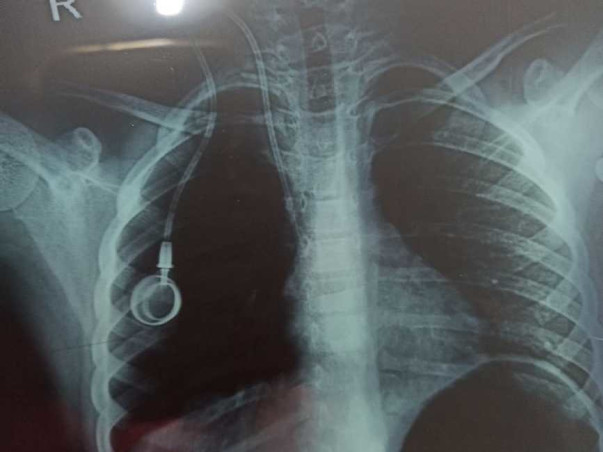

This Girl named Deekshitha M C aged 6 years is suffering from Bone cancer for one year, unfortunately, this little girl's family is not in a condition to fulfill the medical needs to cure her cancer, her father is working as a clerk in a small steel store.

The treatment would cost her more than 20 Lakhs. however, she is already gone through 2 cheemo Sessions, needs to undergo for further sessions.

attached are all the proofs with the estimated bill from the hospital